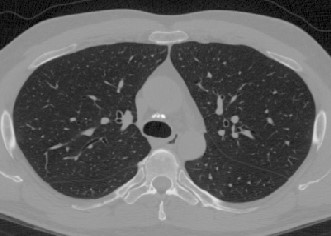

To illustrate the patterns in the radiomic biomarker information obtained across the range of disease, we examine the values from three representative individuals, from healthy, mildly abnormal (Sarc A), and very abnormal (Sarc B) CT scans. As disease becomes more apparent on the CT slices (from healthy to very abnormal) (Figure 1), the values for Moran’s increase. In contrast, the values for fractal dimension and Geary’s C decrease (Tables 3, 4, 5). An increase in Moran’s and a decrease in Geary’s C are indicative of more positive spatial autocorrelation; a decrease in fractal dimension is indicative of smoother structures. The trend in these parameters are clinically important, since we expect to see more positive spatial autocorrelation and smoother structures in CT slices as disease worsens.